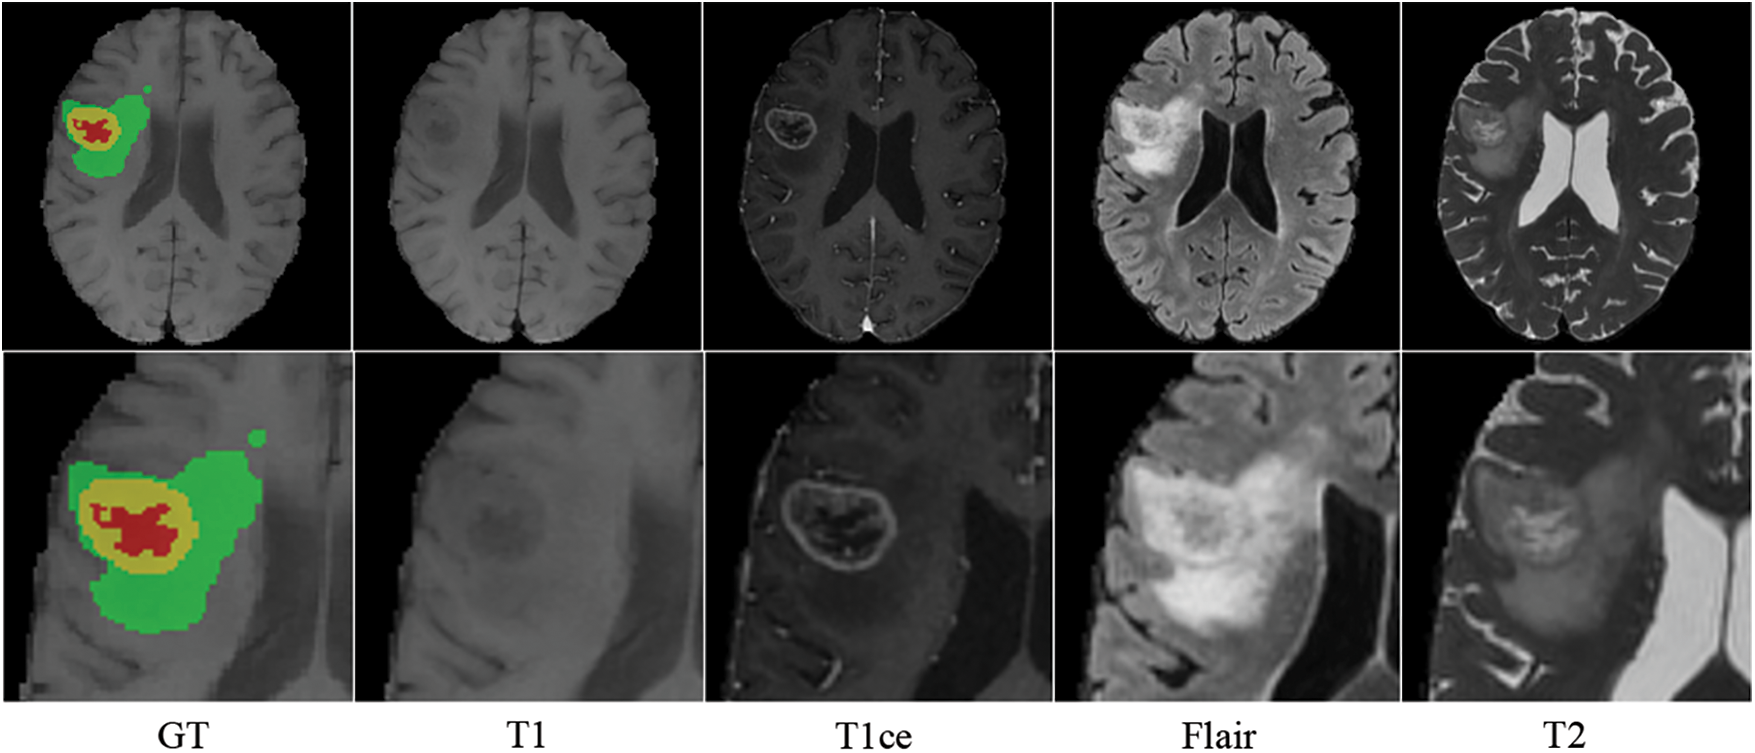

MRI creates distinct modal sequences by altering transverse and longitudinal relaxation [15]. T1-weighted imaging sequence (T1), T2-weighted imaging sequence (T2), T1-weighted contrast-enhanced (T1ce), and fluid-attenuated inversion recovery sequence (Flair) are the most frequently used MRI sequences in clinical practice. The morphological and pathological information on MRI images are complementary: T1 displays the anatomical structure of brain tissues; T2 is related to the tissue’s water content and is used to enhance the lesion area and locate the brain tumor; T1ce displays the interior of the tumor and distinguishes the enhanced tumor core from the gangrenous portion; and Flair inhibits intracranial cerebrospinal fluid and reveals the edge of the peritumoral edema [16]. Different MRI sequences reveal distinct manifestations of brain tissue, which is crucial for diagnosing brain tumors. Fluid and mucus appear as low signals on T1 and high signals on T2 images; adipose appears as high signals on both T1 and T2 images; and lesions appear as either isointense or hypointense on both T1 and T2 images [17]. Therefore, specialists can use T1 and T1ce sequences to observe the tumor core without peritumoral edema and T2 and FLAIR images to highlight the entire tumor with peritumoral edema [18]. Inspired by clinical knowledge and how experts identify tumors from MRI images, we expect the model to learn structural and pathological information about brain tumors based on correlated MRI images’ characteristics. As shown in Fig. 1, brain tumors typically consist of enhancing tumors (Yellow), peritumoral edema (Green), and the gangrenous portion (Red). The T1 image emphasizes the brain’s structure, with the lesion region appearing relatively blurry and the tumor core appearing dim. The enhanced brain tumor region with profuse blood flow is highlighted on the T1ce image. In tasks involving the segmentation of brain tumors, the segmentation of enhancing tumors is relatively tricky. Therefore, combining T1 and T1ce images makes it possible to distinguish the tumor cores with less affection from peripheral edema. Flair images suppress cerebrospinal fluid and enhance the contrast between the lesion and cerebrospinal fluid compared to T2 images. Integrating T2 and Flair images can locate lesions more precisely and recognize the boundaries of edematous regions. This paper separates the input MRI images into two correlated pairs: the first contains T1 and T1ce images, and the other contains T2 and Flair images. This procedure enables more targeted learning and enhances tumor segmentation accuracy.

Figure 1: Four modalities of MRI images of the same patient (axial slice)